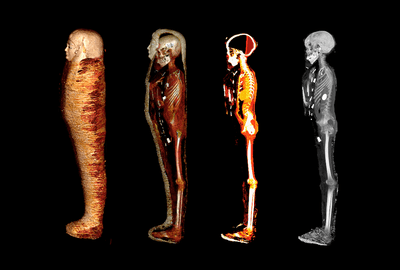

In a new study, archeologists used computerized tomography (CT) scans to study the mummy of the so-called Golden Boy. They found that the remains belonged to a teenage boy who was clearly of high socioeconomic status some 2,300 years ago in ancient Egypt.

.jpg.png)

Their work suggested he stood at around 128 centimeters (4 feet 2 inches) tall. Based on the degree of bone fusion and the fact his wisdom teeth hadn’t yet emerged, the researchers believe he was no older than 15 years old.

Typical of ancient Egyptian mummification techniques, his brain had been removed through the nose and his skull was pumped with resin. All of his vital organs had been removed through an incision, except for his heart which remained in his chest.